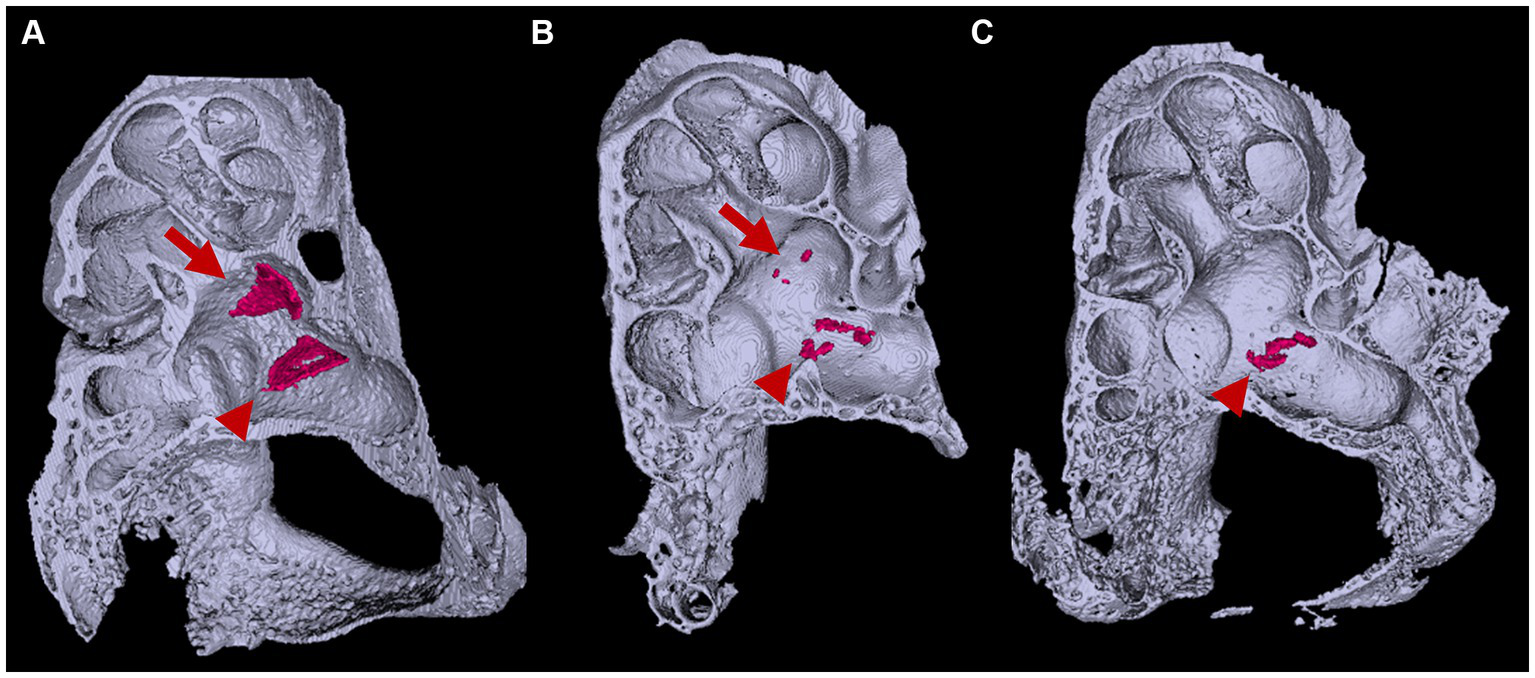

Figure 6

Three-dimensional appearance of otoconia in the otic capsule. Three-dimensional appearances of (A)Slc26a4Δ/+ and (B,C)Slc26a4Δ/Δ otic capsules at P8. Arrows and arrowheads indicate otoconia aggregates in the saccule and utricle maculae, respectively. The surface-rendering technique creates triangular aggregates of the otoconia (red) in the saccule and utricle maculae in Slc26a4Δ/+ mice ears. By contrast, several to a dozen small aggregates are observed in the utricle in Slc26a4Δ/Δ mouse ears, corresponding to giant otoconia. The otoconium in the saccule are few or absent (B,C).

In Slc26a4-deficient mice, the otolith organs exhibit a marked lack of regular otoconia, alongside the occasional presence of abnormally large, or giant, otoconia (Everett et al., 2001; Ito et al., 2020; Watanabe et al., 2023) (Figure 5). Otoconial formation in these mice starts around E14.5, with a peak in mineralization rates occurring between E15 and E16 (Anniko, 1980; Anniko et al., 1987; Lowenstam and Weiner, 1989). It is noteworthy that otoconia undergoes a continuous turnover process. In this process, supporting cells in the otolith organs act as the site of generation, while dark cells function as the absorption site. The formation of giant otoconia is hypothesized to stem from the dissolution and reaggregation of smaller otoconia, likely due to biochemical abnormalities in the endolymph (Dror et al., 2010).

In the Slc26a4-deficient mouse model, a distinctive pattern of otoconial development is observed. By P8, several to approximately 20 giant otoconia are found within the utricle, whereas the saccule typically exhibits a complete absence or contains only 1 or 2 otoconia (Ito et al., 2020; Watanabe et al., 2023) (Figure 6). As the mice age, these otoconia not only enlarge further but also decrease in number (Ito et al., 2020). Under normal circumstances, otoconia, secured by a filamentous matrix, are confined above the sensory epithelium of the saccule and utricle, preventing their displacement into other endolymphatic spaces. However, in the Slc26a4-deficient mice, giant otoconia demonstrate notable instability on the otoconial membrane, often dislodging during experimental processing. This instability is evidenced by the frequent observation of abnormal, ectopic otoconia in the semicircular canals and their cristae in histological sections (Dror et al., 2010), indicative of a disruption in normal Slc26a4 expression.